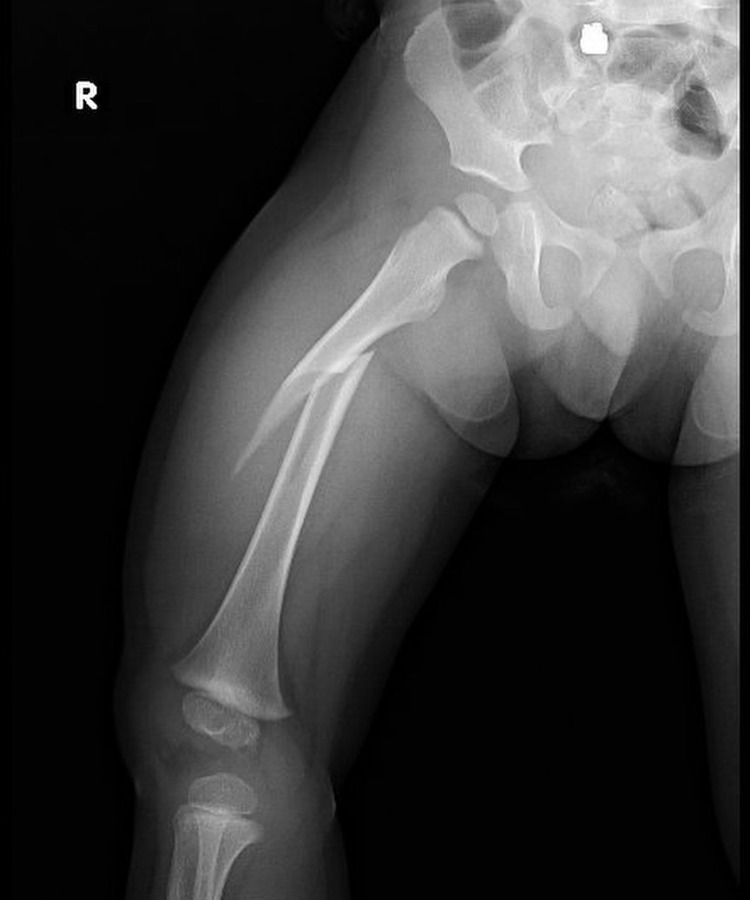

Técnicas quirúrgicas pediátricas restauran función y apariencia de extremidades con lesiones graves o deformidades congénitas, buscando mejorar funcionalidad y estética.

Las fracturas en niños son comunes y pueden afectar su crecimiento si no se tratan debido a las características únicas de sus huesos en desarrollo.